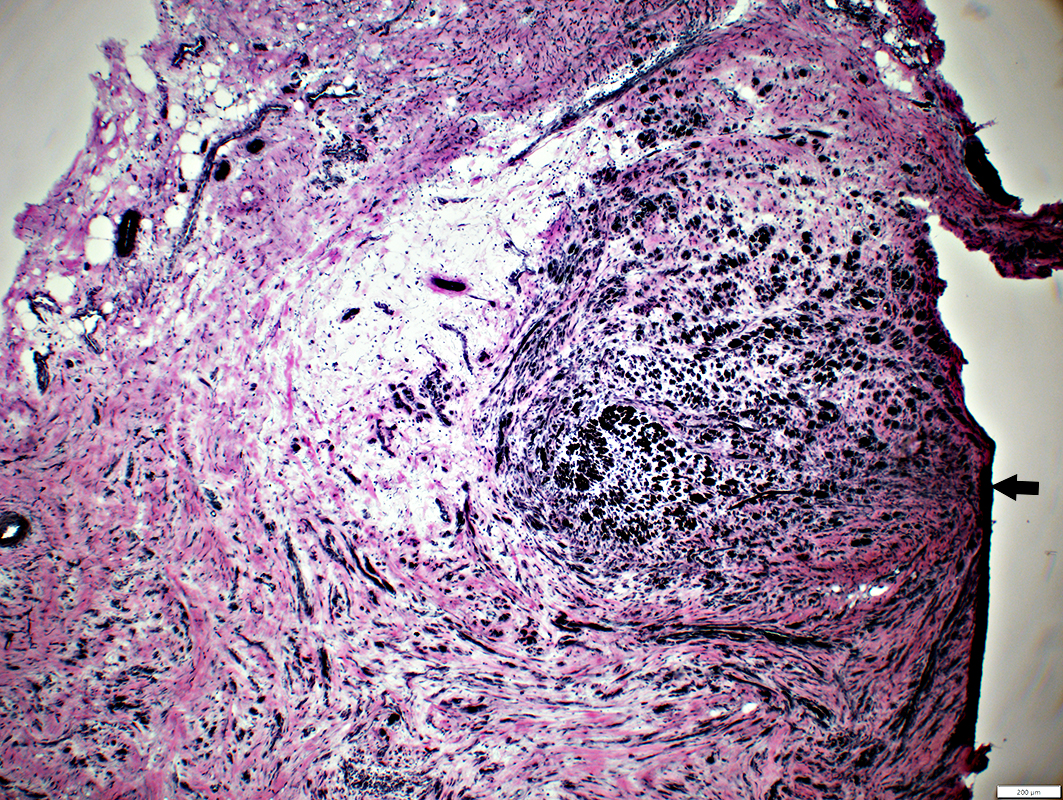

Regeneration: Aberrant Fascicles

Minifascicles

Varied sizes & orientations

H&E stain

Post-regeneration: Small fascicles with varied size and orientations

Neuroma: Multiple small fascicles containing myelinated axons

Neuroma

Varied sizes & orientations of axon clusters (fascicles)

Varied numbers of myelinated & non-myelinated axons in fascicles

Varied numbers of axons in fascicles

Several small fascicles separated by connective tissue

Each fascicle is surrounded by perineurium, 1 or several layers